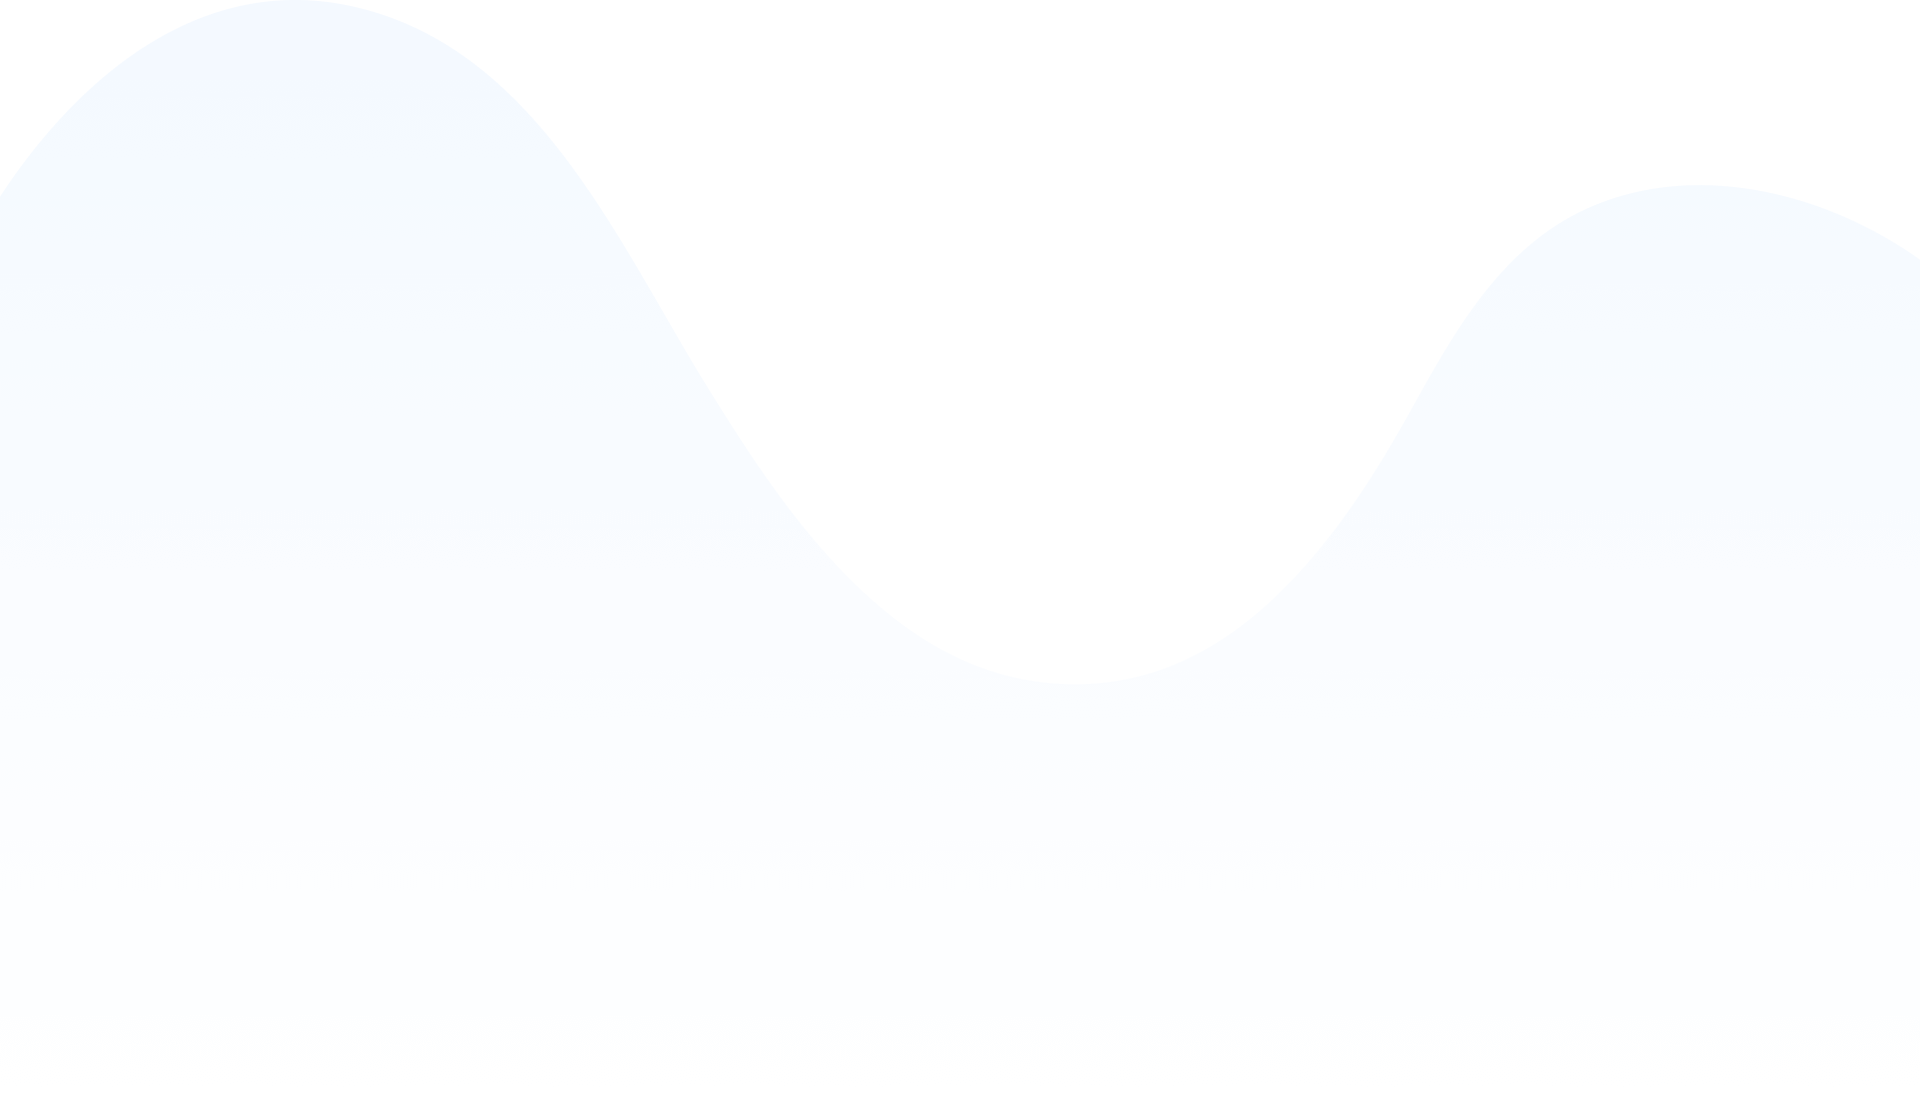

Following our team expertise in healthcare products, we’ve outlined clear & clean UX concepts and started with careful UI creation leveraging native mobile technologies capabilities.

One of the main differentiators in Healthcare is the UX of the product – many companies develop functional telemedicine apps but they often lack clear & simple UX with sophisticated design in place – that what Interexy’s team focused on during the design process.

We also knew that the design should be robust & responsive to the standards of B2B healthcare space – here at Interexy we did research on competitive telemedicine products taking the best UI & UX solutions and applying them with MedKitDoc.

One of the main UX challenge was the fact that MedKitDoc is heavily hardware-integrated – we had a range of devices to connect with the app via Bluetooth and needed to provide seamless user experience in case of connection issues.

Interexy’s UX & UI team carefully went through the most challenging parts of the product iteratively creating a range of prototypes to finalize the UX and user interface design part to fit the product’s objectives and users’ expectations.

One of the challenges with the UX part of the product was creating a separate flow for physicians & adapting it to the standards of healthcare software tools making the design beautiful and clean at the same time.

Many healthcare products that being used by practicing physicians nowadays lack simplicity & beautiful UX and UI solutions and with MedKitDoc we had a goal to disrupt industry standards and create an iOS app that will distinguish itself from the similar products in the industry with its’ modern design approach.

Implementation of design pixel-perfectly & connection of the UI with the user experienced outlined by clickable prototype provided at the completion of design stage were the most important points during the UI implementation part of the project.

We set a high-end goal with changing how healthcare is treating the user experience & user interface with the software products and apps especially and wanted to provide similar to popular social apps type of user experience.